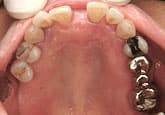

さらに3週間後

歯石除去

歯石が見えてきたので、歯石を除去しました。

健康な歯肉に回復しました。